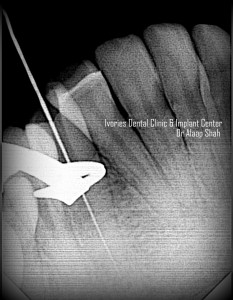

- Role of a pre-operative radiograph

- Role & application of apex locators[J morrita, Propex2] Vs use of xrays

- CASE DISCUSSION & ESTABLISHING DIAGNOSIS WITH RADIOGRAPHS

- WORKING LENGTH DETERMINATION WITH APEX LOCATORS